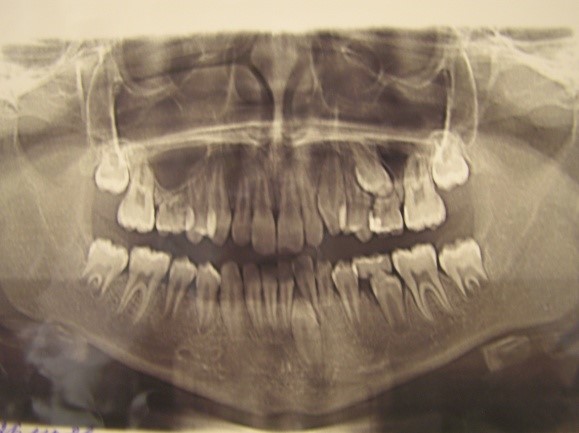

Pic.24. Transposition of 33 and 32.